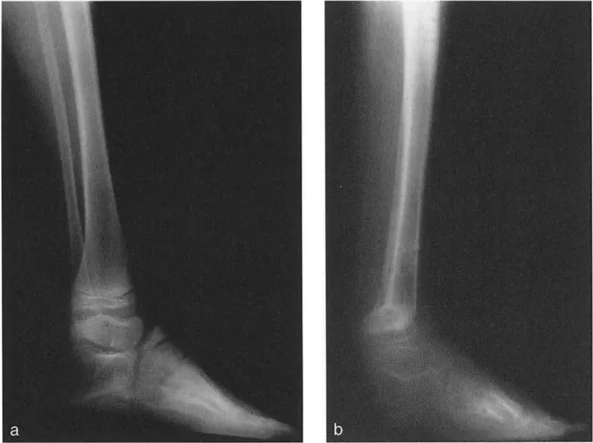

التصوير الإشعاعي المتقدم

التصوير الإشعاعي هو الأداة الأساسية لتأكيد التشخيص وتحديد تفاصيل التشوه.

* الأشعة السينية (X-rays) الواقفة لكامل الطرف السفلي: هذه الأشعة ضرورية لتقييم المحاذاة الكلية للطرف السفلي تحت تأثير وزن الجسم. يطلب الأستاذ الدكتور محمد هطيف صورًا شعاعية كاملة الطول للساق أثناء الوقوف (Full-length standing alignment films) لتقييم المحور الميكانيكي للساق وتحديد زوايا المفاصل بدقة.

* الأشعة السينية الجانبية والامامية الخلفية للكاحل: تُظهر هذه الصور تفاصيل مفصل الكاحل نفسه، بما في ذلك زاوية القصبة الأمامية البعيدة (ADTA) وزاوية القصبة الوحشية البعيدة (LDTA)، وهي زوايا حاسمة لتحديد التشوه في المستويين الأمامي والسهمي.

أنواع جراحات قطع العظم فوق الكاحل (Supramalleolar Osteotomy)

جراحة قطع العظم فوق الكاحل (SMO) هي الإجراء الأكثر شيوعًا لتصحيح تشوهات قصبة الساق البعيدة. تتضمن هذه الجراحة قطعًا دقيقًا في عظم الساق (القصبة) فوق مفصل الكاحل مباشرة، ثم إعادة محاذاة العظم وتثبيته في الوضع الصحيح. هناك عدة أنواع من هذه الجراحة:

1. قطع العظم الإسفيني الفاتح (Opening Wedge Osteotomy):

2. قطع العظم الإسفيني المغلق (Closing Wedge Osteotomy):

3. قطع العظم القوسي البؤري (Focal Dome Osteotomy):

• يتم عمل قطع منحني في العظم، مما يسمح بتصحيح